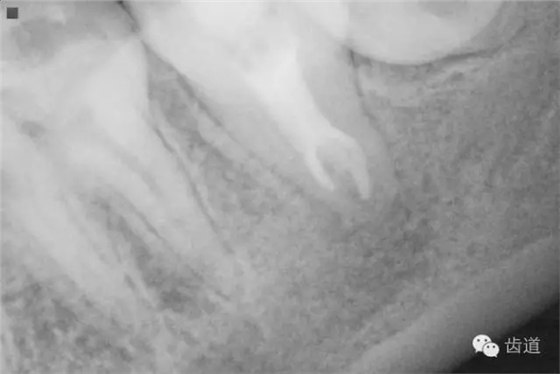

檢查:術(shù)后半年回訪,37牙體及合面嵌體未見(jiàn)缺損及裂紋,邊緣密合,未探及繼發(fā)齲,探痛-,叩痛-,松動(dòng)-,冷水刺激痛-,未探及牙周袋及附著喪失,牙齦無(wú)紅腫,X線片檢查示根尖周膜連續(xù)性恢復(fù),根尖周透射影消失。

2. 術(shù)后半年X線檢查,可見(jiàn)根尖周膜連續(xù)性恢復(fù),根尖周透射影消失